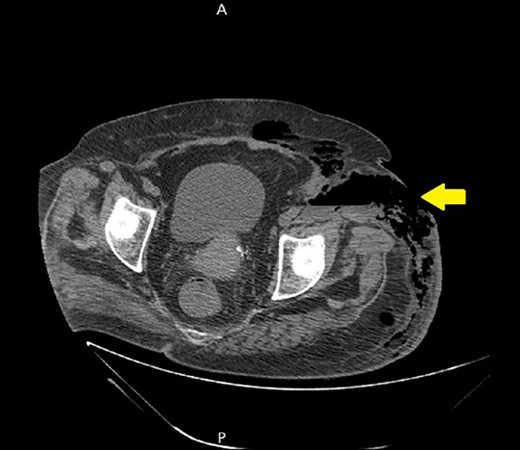

Ultrasound showed extensive subcutaneous soft tissue edema with hyperechoic areas seen in the proximal anterolateral part of the thigh. The initial diagnosis of the condition was a left iliopsoas abscess. Due to the severity of the patient’s symptoms, a non-contrast abdomen and pelvis computerized tomography (CT) scan was done (Fig. 3), which showed a large amount of subcutaneous emphysema within the left flank soft tissues that wrapped anteriorly along the left lower lateral abdominal wall with a small tract of air extending from the left retroperitoneum posterior to the left kidney and extending along the left iliopsoas muscle inferiorly. A skin defect with the underlying abscess collection and air–fluid level was noted (Fig. 4). Another CT scan section saw a soft tissue mass lesion at the distal descending colon (Fig. 5). The abscess drainage was done under CT guidance.

A non-contrast abdomen and pelvis CT scan, which shows a skin defect with underlying abscess collection and air–fluid level, with significant subcutaneous air collection.